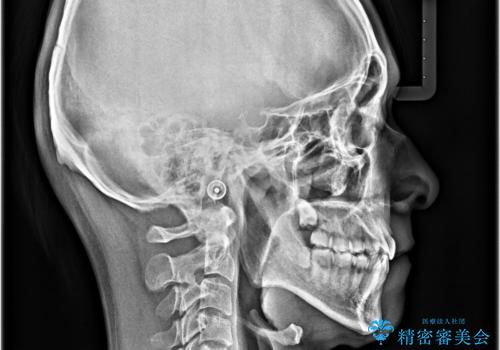

顎が左右にずれた咬み合わせ ハーフリンガルの抜歯矯正

裏側装置での交叉咬合改善は非常に困難なもので、頻繁に装置の脱落がありました。

それでも想定以上に治療期間は長期化せず、咬み合わせも口元も満足のいく仕上がりとなりました。